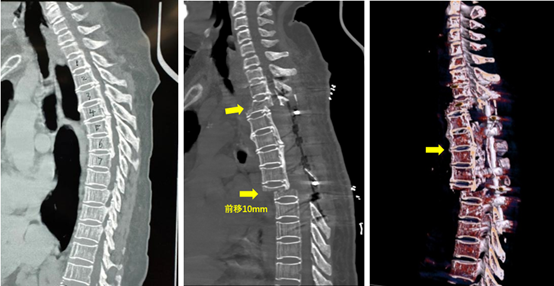

胸椎后路椎体-OPLL复合物可控前移减压融合手术示意

经过充分的围术期准备,以及反复琢磨、推演后,治疗团队决定采用“胸椎椎体-OPLL复合物前移减压技术”为患者进行手术治疗,麻醉科雷晓鸣教授、宋正川教授和赵茜娟医生为患者实施麻醉,手术室张新侠老师配合,李浩鹏主任主刀、蔡璇副主任、张廷教授及赵敏超医生协助,黄亚娟及孙丽君老师全程为患者实施神经电生理监护。胸椎显露、置钉、后方椎板整块切除、椎体截断……,手术依照术前规划有条不紊地进行着,历时6小时,最终5节截断的椎体连同骨化物顺利被推向前方,一切和术前模拟的一样,神经监护显示脊髓安全,这一刻,手术团队终于轻舒一口气,手术成功了!手术后患者麻醉清醒就感到肢体麻木和肌肉力量明显好转。术后复查3D-CT显示椎体连同骨化物前移约10mm,脊髓减压充分,患者目前正在积极康复治疗中。经过文献查新检索,国外未见相关报道,国内目前只有上海和广州两家国内顶级医院2022年报道过类似的个案,其手术设计思路与李浩鹏主任不谋而合,我院开展的此例手术属中西部首例。同时,我方设计经椎体截骨稳定性更佳,后期更易获得坚强骨融合,患者可早期下地活动。

术后影像显示手术节段胸椎整体前移10mm,脊髓减压满意